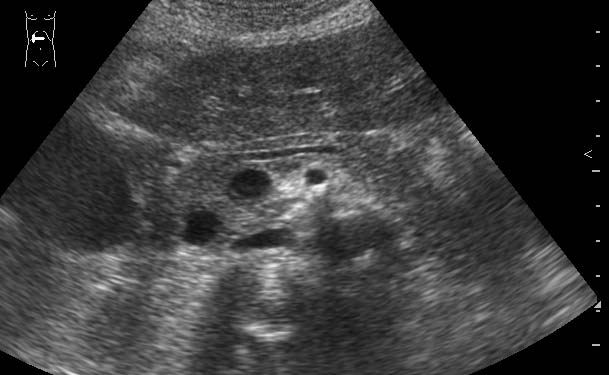

УЗИ панкреас, болевой приступ

Молодая женщина с болями в животе.

Какое заключение можно сделать по этой сонограмме?

Очаговые образования головки ПЖ (кисты?) Рек-но КТ.

Инга, ну где здесь кисты? Где здесь очаговые изменения? Вы хотите получить повторный 2-хнедельный срок?Инга писал(а):Очаговые образования головки ПЖ (кисты?) Рек-но КТ.

Вспоминаем нормальную анатомию!

Жаль нет снимка во взаимоперпендикулярной плоскости.Можно предположить аневризму брюшного отдела аорты.

Холодно. Аневризмы брюшного отдела аорты здесь нет.Лилия писал(а):Жаль нет снимка во взаимоперпендикулярной плоскости.Можно предположить аневризму брюшного отдела аорты.

Конечно же не норма.Инга писал(а):"Срок" бы не помешал ...![]()

По моему это расширенный Вирсунгиев проток,нужно исключать патологию дуоденального сосочка-ФГС